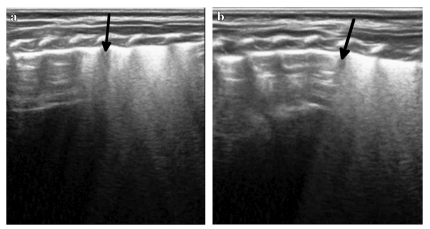

Дополнительно обращают внимание на наличие или отсутствие характерных вертикальных сигналов (B-линий) (см. рис. 3). Их наличие, как правило, исключает пневмоторакс, но их отсутствие само по себе ещё не подтверждает диагноз.

Рис.3 На первом изображении (a) видно ровные параллельные линии — это значит, что лёгкое не двигается из-за пневмоторакса. Ниже (b) появляется так называемый «признак берега» — участок, где лёгкое всё ещё движется нормально. Граница между этими зонами называется «точка лёгкого» — она показывает место, где начинается пневмоторакс. На рентгене (c) также видно большое скопление воздуха слева, а стрелка указывает на ту же самую границу.

Очень важным признаком считается так называемая «точка лёгкого» — граница между нормальной и изменённой зоной. Её обнаружение практически точно указывает на наличие пневмоторакса, если он не тотальный.